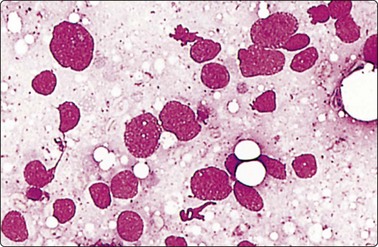

image image

Fig. 5.12 Sinus histiocytosis with massive lymphadenopathy (Rosai-Dorfman disease)

(A) Tissue section showing very large histiocytes harboring many lymphocytes (and some plasma cells) in their cytoplasm, (H&E, IP); (B) Smear showing large histiocytes with intracytoplasmic lymphocytes and plasma cells (MGG, IP).

(Reproduced with permission from van Heerde et al.9)